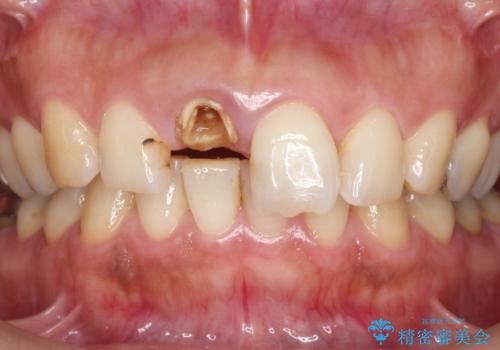

歯の変色 前歯の審美改善

- 前歯の変色の改善を求めて来院されました。

X線写真より、以前に神経の治療が為され変色をきたしている状態であることがわかりました。

根管内の感染は認められないのでセワミッククラウンの製作・装着を行い審美性を改善します。

- 13万円(仮歯・ファイバーコア・ジルコニアクラウンスタンダード)費用は治療当時の料金となります